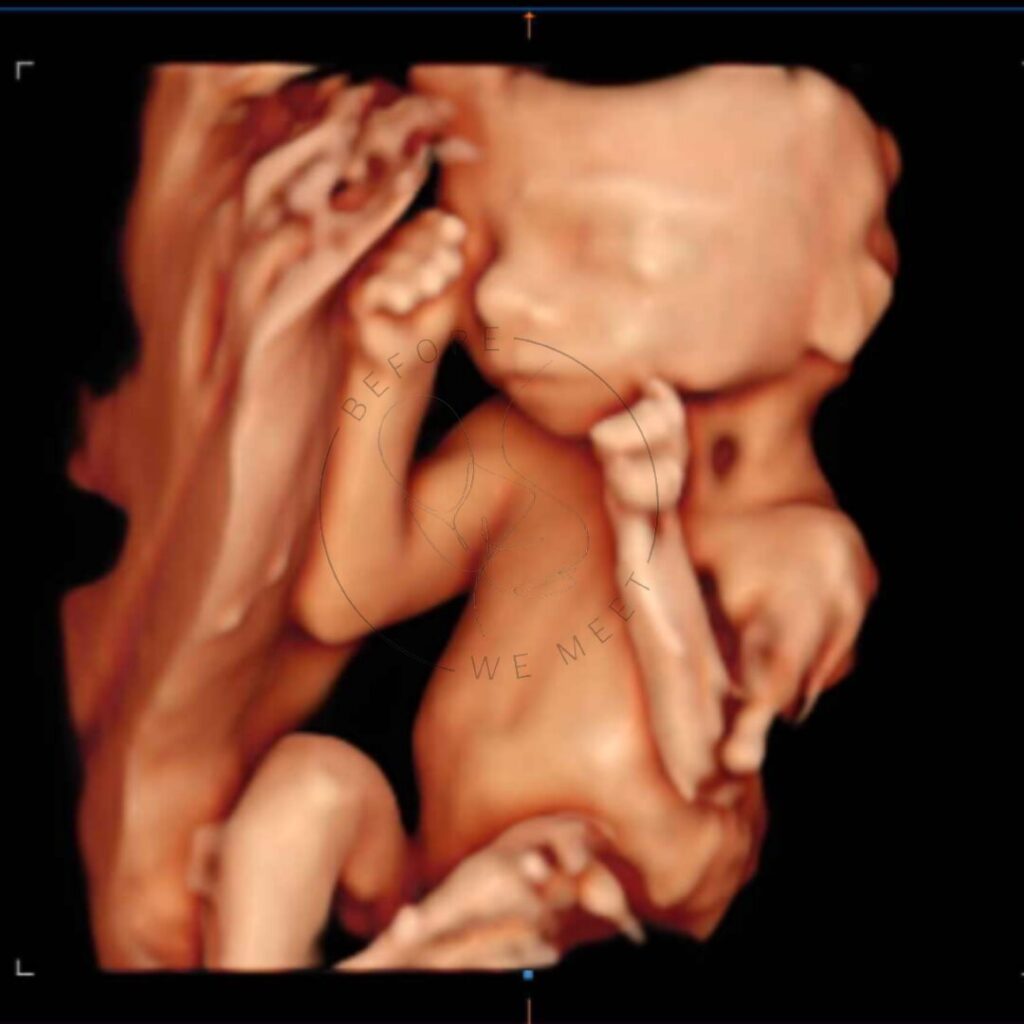

Veel ouders kiezen voor een pretecho als herinnering aan de zwangerschap of om samen met familie of vrienden extra naar de baby te kijken. Bij een 3D- of 4D-echo zien we duidelijk het gezichtje in kleur en zien we soms een lachje of een gaapje!

Een 3D/4D echo is éxtra bijzonder doordat we de baby met al zijn of haar details kunnen zien in stilstaande en bewegende beelden. Op wie lijkt zijn/haar neusje? Heeft hij/zij al bolle wangetjes? Of misschien zien we de baby zelfs wel drinken of lachen? Het laat jou (en ons!) verwonderen hoe magisch het nieuwe leven dat in je buik groeit is!

Iedere periode van de zwangerschap vinden wij even bijzonder, juist omdat je per maand zoveel verschil kunt zien. Echter is herkenning van het gezichtje het mooiste tussen de 24e en 30e week van de zwangerschap en afhankelijk van hoe de baby in je buik ligt, of hij/zij zich verstopt achter handjes, voetjes of de placenta en hoeveel vruchtwater er aanwezig is. Mocht het daardoor niet lukken om de baby goed in beeld te krijgen dan mag je nogmaals kosteloos terugkomen voor een echo van 20 minuten.